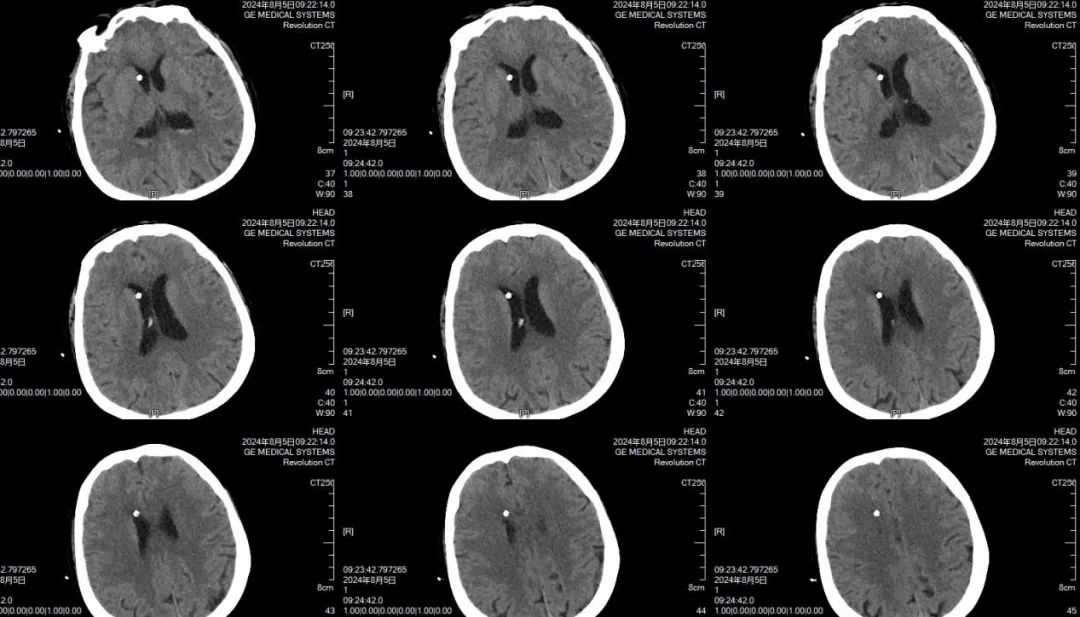

郑维超主任与黄佳荣医生认真听取了家属对病情的详细介绍后,以极其严谨、科学的态度对病情进行分析诊断。他们深知,小脑出血位置特殊,稍有不慎便会危及患者生命。但考虑到患者目前已陷入昏迷状态,为了更加准确地掌握病情变化,他们果断决定对患者再进行一次 CT 检查。11 点 53 分,头部 CT 复查结果显示,小脑出血较之前明显增多,并且伴有急性脑积水。患者病情万分危急,生命危在旦夕,每一秒的拖延都可能带来不可挽回的后果。郑维超主任立即会同神经外科专家组,展开了一场紧张而激烈的病情讨论。凭借着丰富的临床经验和专业知识,迅速制定出一套严谨周密的救治方案。经过深思熟虑,郑维超主任决定立即对重症患者依次进行脑室外引流手术、小脑血肿清除手术以及后颅窝骨瓣减压手术。

凌晨4时,当刘先生看到母亲面容安稳平和的被推出手术室,他的泪水再次夺眶而出,他双手合十,一次又一次地表达着内心深处的感恩之情。患者术后4小时,再次进行头部 CT 复查,结果显示脑室大小已恢复正常,小脑血肿被清理得极为干净。刘先生面向在手术室参与抢救他老母亲生命的全体医务人员,竖起大拇指,微微点头,以无声的方式传达着内心的感激与敬佩之意。